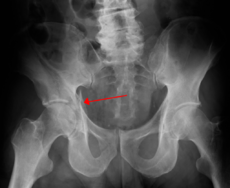

Acetabular fracture (red arrow)

Right acetabular fracture (arrow)